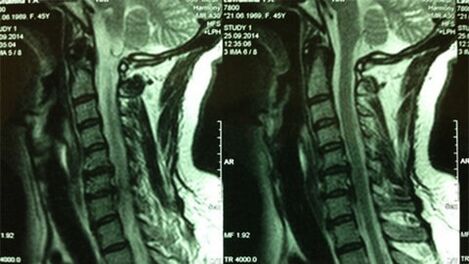

- X -RAY OF DEPARTAMENTULUI CERVIX; În faza inițială a procesului, RMN -ul departamentului cervical va fi mai informativ - va asigura o vizualizare ridicată a țesutului solid și moale - arată starea discurilor intervertebrale, prezența osteofitelor, deformații, deteriorarea rădăcinilor nervoase și a vaselor de sânge; evaluează starea ligamentelor, mușchilor, țesutului osos;